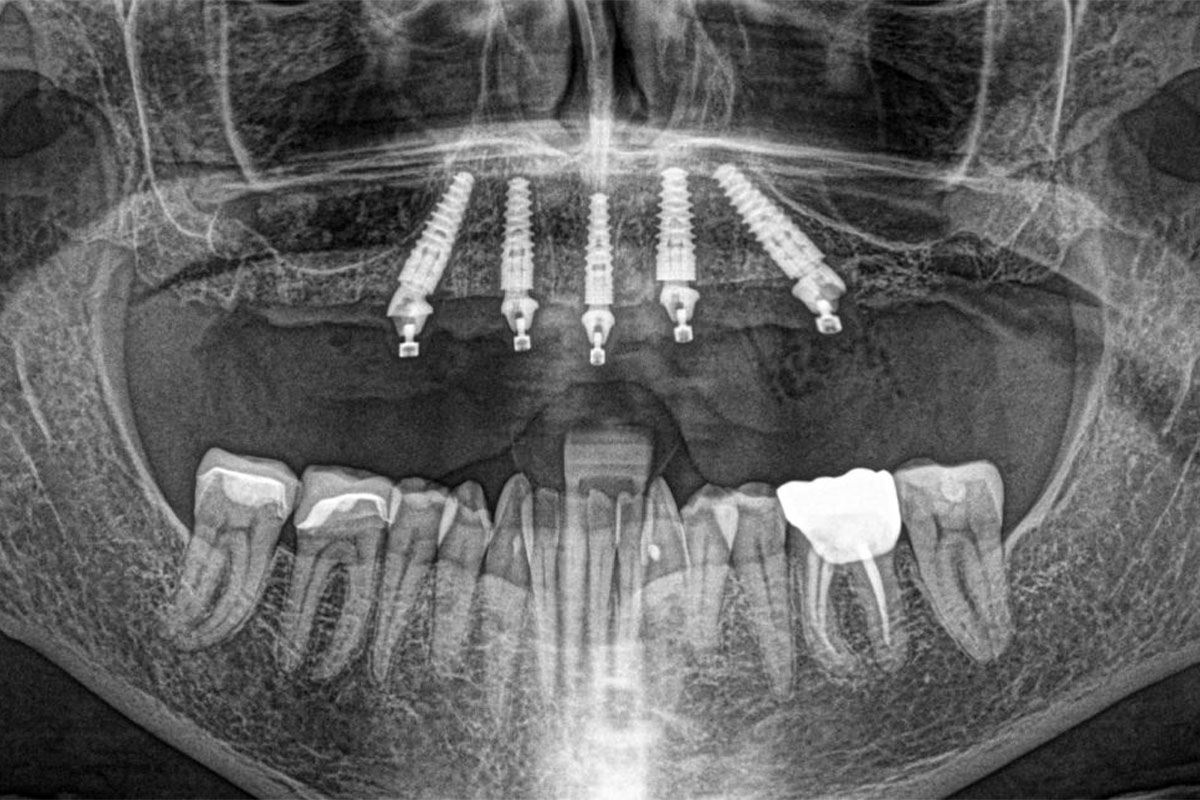

3. Taking digital X-rays, CT scans, or panoramic imaging to get a detailed view of your jaw structure.

2. Once you’re comfortable, our dentist will make small incisions (cuts) in your gums to expose the jawbone. We then insert four titanium implants into your jaw at specific angles. Two implants are placed vertically at the front of your jaw, and the other two are placed at a 45-degree angle in the back. This approach ensures maximum stability, even if you have reduced bone density.